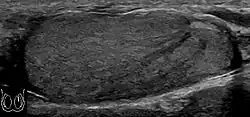

Fig. 3. Seminoma. (a) Seminoma usually presents as a homogeneous hypoechoic nodule confined within the tunica albuginea. (b) Sonography shows a large heterogeneous mass occupying nearly the whole testis but still confined within the tunica albuginea, it is rare for seminoma to invade to peritesticular structures.

Approximately 95% of malignant testicular tumors are germ cell tumors, of which seminoma is the most common. It accounts for 35%–50% of all germ cell tumors. Seminomas occur in a slightly older age group when compared with other nonseminomatous tumor, with a peak incidence in the fourth and fifth decades. They are less aggressive than other testicular tumors and usually confined within the tunica albuginea at presentation. Seminomas are associated with the best prognosis of the germ cell tumors because of their high sensitivity to radiation and chemotherapy.

Seminoma is the most common tumor type in cryptorchid testes. The risk of developing a seminoma is increased in patients with cryptorchidism, even after orchiopexy. There is an increased incidence of malignancy developing in the contralateral testis too, hence sonography is sometimes used to screen for an occult tumor in the remaining testis. On US images, seminomas are generally uniformly hypoechoic, larger tumors may be more heterogeneous [Fig. 3]. Seminomas are usually confined by the tunica albuginea and rarely extend to peritesticular structures. Lymphatic spread to retroperitoneal lymph nodes and hematogenous metastases to lung, brain, or both are evident in about 25% of patients at the time of presentation.